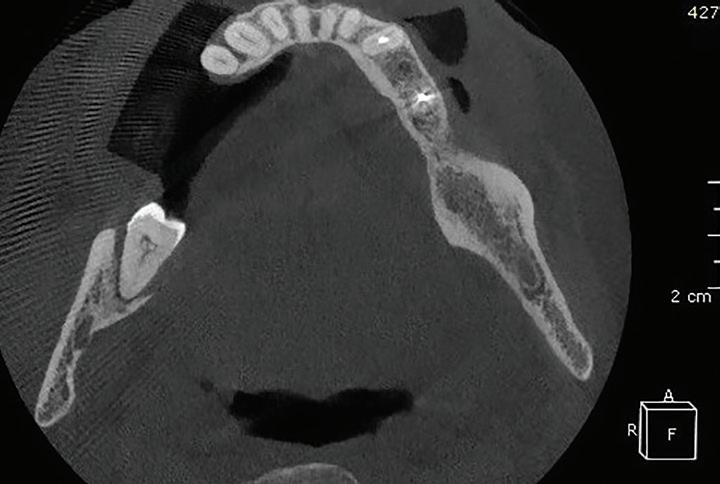

After tooth extraction and socket preservation, patients heal for at least 3 to 4 months. Once the healing process is complete, among the most important procedures for implant planning are cone beam computed tomographic (CBCT) and intraoral scans. The CBCT scan is a 3-dimensional (3D) radiograph that shows the patient’s bone in ways that cannot be seen on 2-dimensional images such as periapical, bitewing, or panoramic radiographs. The use of CBCT scans for implant cases is becoming common because of the important information provided, including bone height, bone width, and the location of arteries, veins, nerves, and other important anatomical features.2

In addition, CBCT images can be used to assess bone density. Bone density ranges from D1 to D4.3 The density is measured in a ratio of cortical-to-cancellous bone. Cortical bone, which makes

up the outer portion of the bone, is dense and has low vascularity. Cancellous bone, which makes up the inner portion of the bone, is not dense and has higher vascularity. D1 bone consists of a high percentage of highly dense cortical bone and minimal to no cancellous bone. D4 bone has a high percentage of low-density cancellous bone and little to no cortical bone. In bone that is more cortical and more dense, the clinician will generally make a larger osteotomy to reduce the stress put on the dense bone. In bone that is less dense and more trabecular, the clinician can make a more undersized osteotomy to ensure good primary stability of the implant. Depending on the type and density of bone found on the preoperative CBCT, the clinician can modify the implant placement technique to adjust for the findings. In my experience, the density of grafted sites is usually classified as D2, but this can vary depending on the type of graft used (Fig 1 and 2).

Fig 1. CBCT images confirm healing of the extraction site after grafting. Fig 2. An occlusal CBCT view reveals the density of the healed graft.